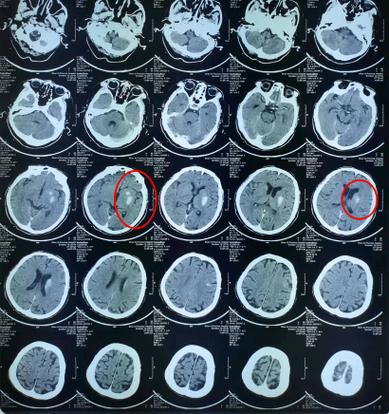

(图片来源网络,侵删)

“脑CT基底节左侧脑梗”是一个严肃的诊断,意味着左侧大脑的交通枢纽发生了堵塞,导致了右侧身体可能出现功能障碍。

这份报告包含了三个关键信息点:检查方法(脑CT)、病变位置(基底节左侧)、病变性质(脑梗)。

病变位置:基底节左侧

- 基底节是什么? 您可以把大脑想象成一个复杂的城市,基底节就是这个城市里非常重要的“交通枢纽”和“控制中心”之一,它位于大脑的深部,负责协调运动、控制肌肉张力、以及参与一些高级认知功能。

- 左侧意味着什么? 大脑的左半侧主要控制右侧身体的功能,左侧基底节发生梗塞,通常会导致对侧(即右侧)身体出现症状。

病变性质:脑梗(脑梗死)

- 脑梗是什么? “梗”堵塞”的意思,脑梗,全称是“脑梗死”,也叫“缺血性脑卒中”,通俗地讲,就是给大脑某部分区域供血的血管被堵住了,导致该区域的脑细胞因为缺血缺氧而死亡。